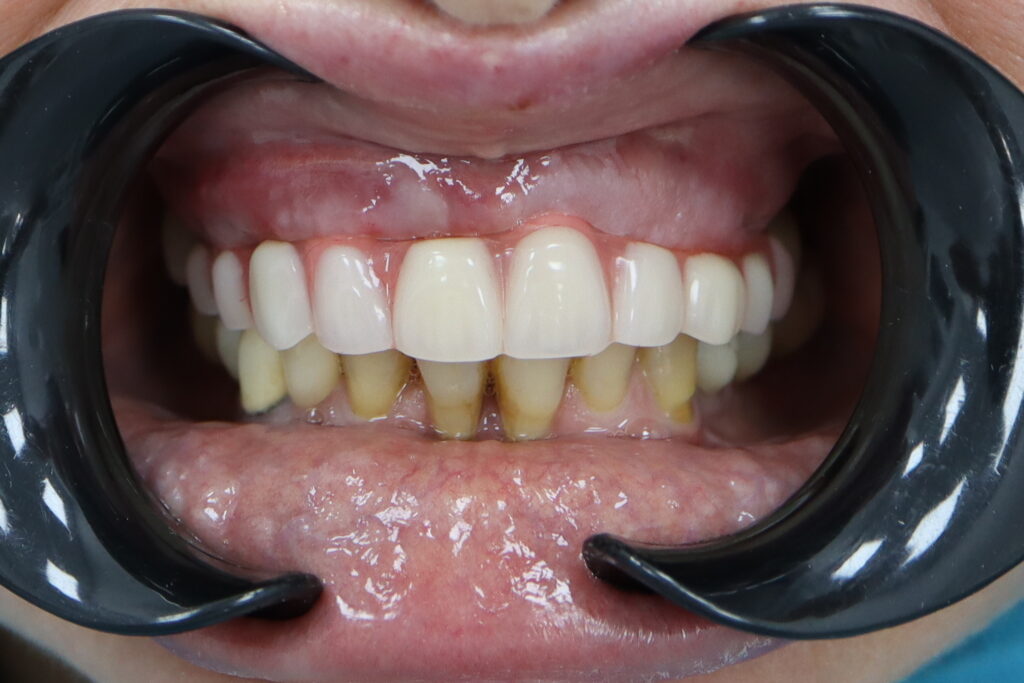

Результаты

результат имплантации